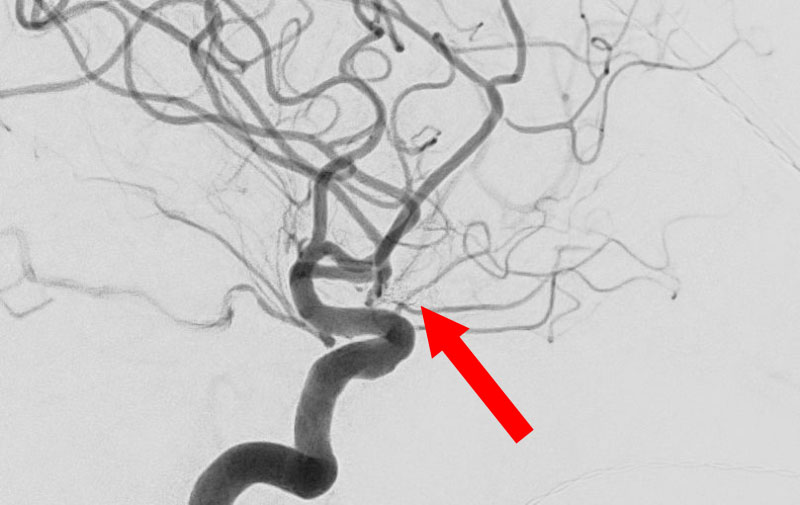

くも膜下出血

左中大脳動脈瘤破裂

40代

救急外来

No.1596 手術前